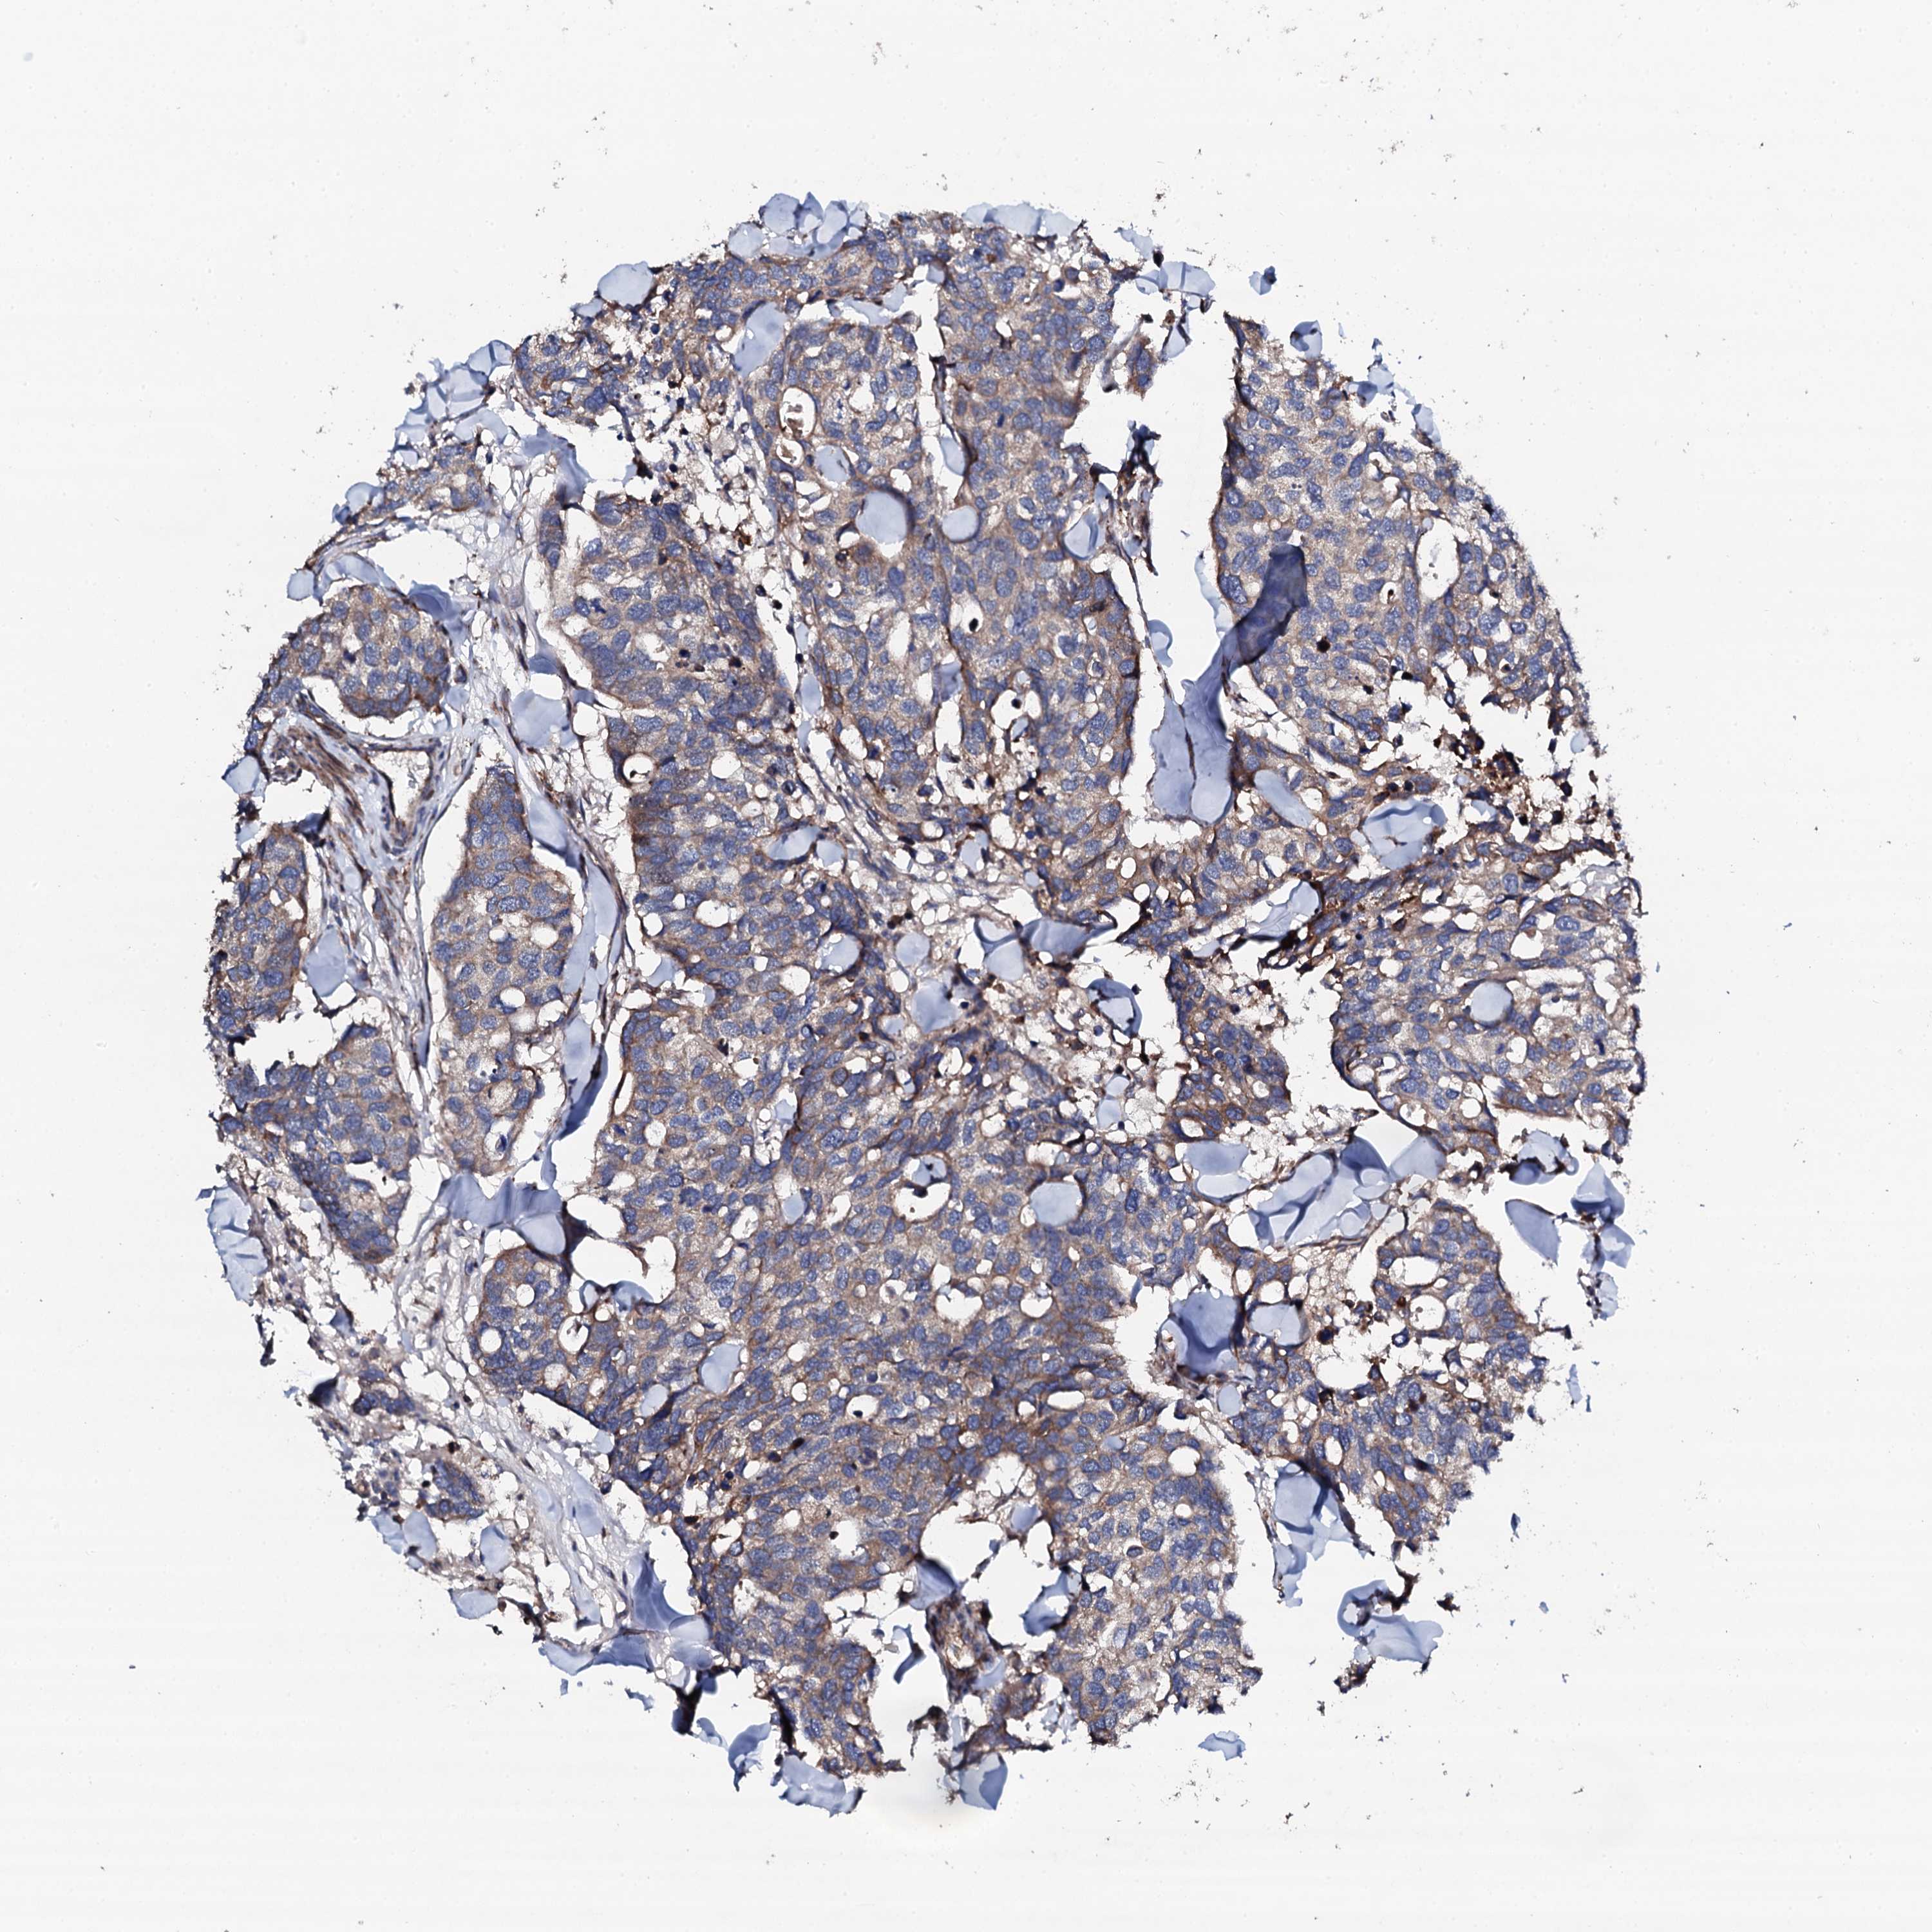

CANCER BREAST CANCER Show tissue menu

BRCA TCGA BRCA VALIDATION PROTEIN EXPRESSION